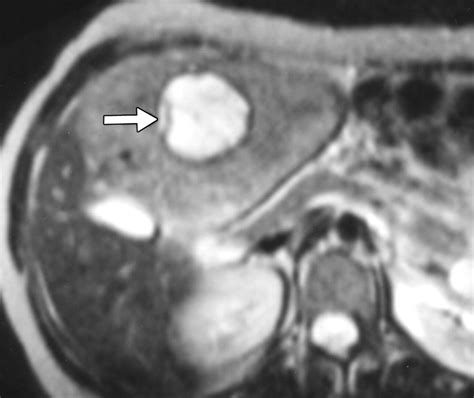

• Magnetic Resonance Imaging (MRI): MRI uses magnetic fields and radio waves to produce detailed images of the liver. It is often the preferred method for diagnosing FNH due to its high sensitivity and specificity.